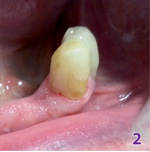

Pacjent, dowiedziawszy się o wszelkich zagrożeniach wynikających z zaniechania leczenia chirurgicznego, miał czas na podjęcie decyzji co do dalszego postępowania. Po tygodniu zgłosił się do gabinetu stomatologicznego, gdzie za jego zgodą został wykonany zabieg chirurgiczny (ryc. 2).

Wynik badania histopatologicznego: epulis fibrosa, excisio completa. Po całkowitym wygojeniu tkanek miękkich pobrano wyciski i wykonano wcześniej zaplanowane protezy zębowe.